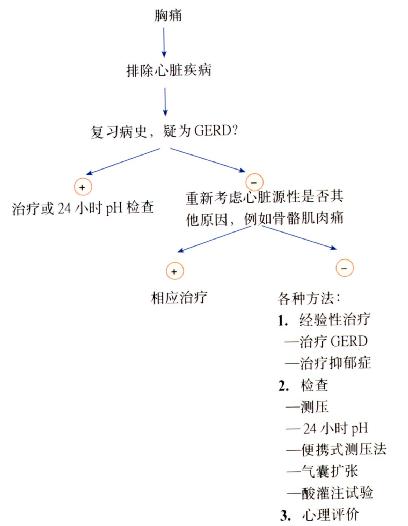

诊断措施(图3.14)

图3.14诊断胸痛的程序。